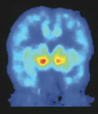

The nucleus accumbens, hand drawn in red on the MRI brain scan (left) of a control subject, produces feelings of pleasure. When carfentanil, an opiate-like drug, was given, it bound to opioid receptors in the region, as seen in red on the PET scan (right). When subjects drank alcohol, naturally occurring opioids, or endorphins, were released and bound to the same receptors, preventing cartenefil from binding. Image by Science/AAAS

Before drinking, the subjects were given injections of radioactively tagged carfentanil, an opiate-like drug that selectively binds to sites in the brain called opioid receptors, where endorphins also bind. As the radioactive carfentanil was bound and emitted radiation, the receptor sites “lit up” on PET imaging, allowing the researchers to map their exact locations.

The subjects were then each given a drink of alcohol, followed by a second injection of radioactive carfentanil, and scanned again with PET imaging. As the natural endorphins released by drinking were bound to the opioid receptor sites, they prevented the carfentanil from being bound. By comparing areas of radioactivity in the first and second PET images, the researchers were able to map the exact locations — areas of lower radioactivity — where endorphins were released in response to drinking.